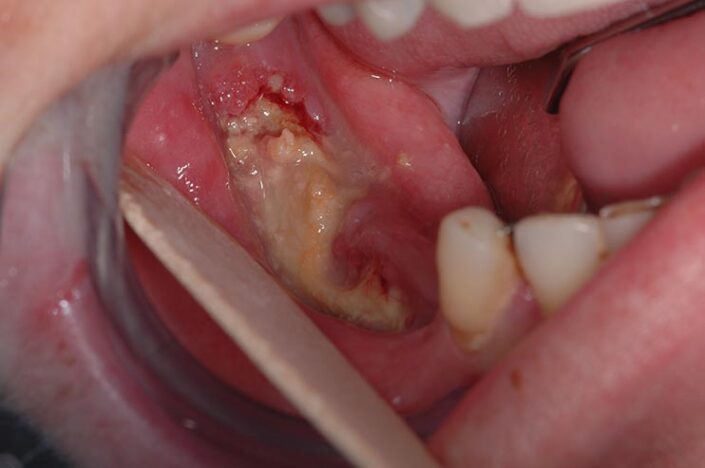

OSTEONECROSI CHIMICA DA IPOCLORITO

Segno clinico maggiore:

- Esposizione osso necrotico (Cavo orale)

Segno clinico minore:

- Alitosi

- Ascesso odontogeno

- Asimmetria mandibolare

- Dolore

- Fistola (intra ed extra orale)

- Fuoriuscita liquido dal naso

- Mobilità dentale

- Secrezioni purulente

- Segno di Vincent

- Trisma

- Tumefazione tessuti molli